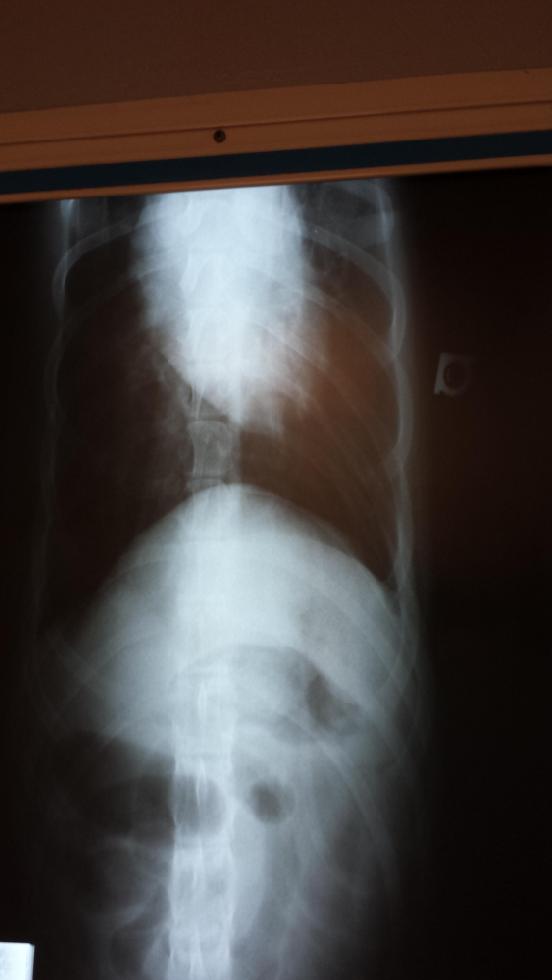

06MAY15/Wednesday... 102 pounds?!?!?... loosing weight... what's with that??? do X-rays and blood work...

hmmmmm... looks llike a hair tie... aka puppy chewing gum...

08MAY15/Friday... 97.5 pounds?!?!?... VCA Emergency Hospital: ultra sound & ACTH blood test confirm... Penny has Addison's Disease VCA WSac Hospital:... Penny gets 1st Addison's Disease maintenance shot and going forward, Penny MUST get an Addison's Disease maintenance shot of Percorten-V (  ) every 28 days plus a daily dose of Prednisone to prevent "crashing"... then death...